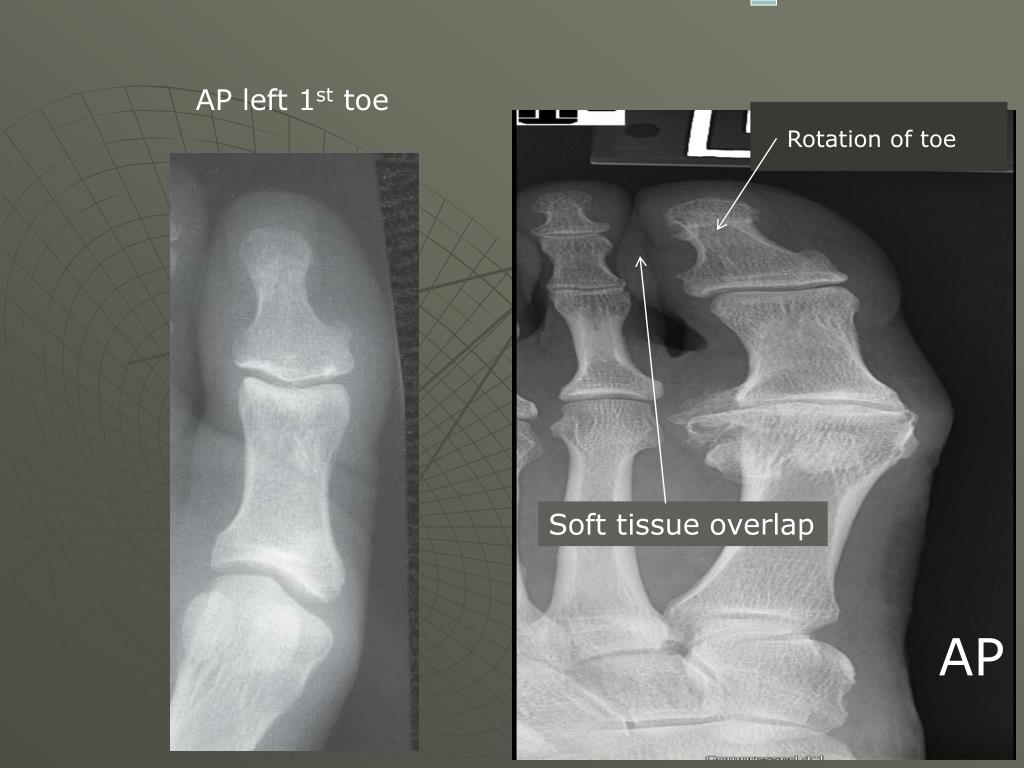

6. AP left 1st toe Rotation of toe Soft tissue overlap AP

Film Critique